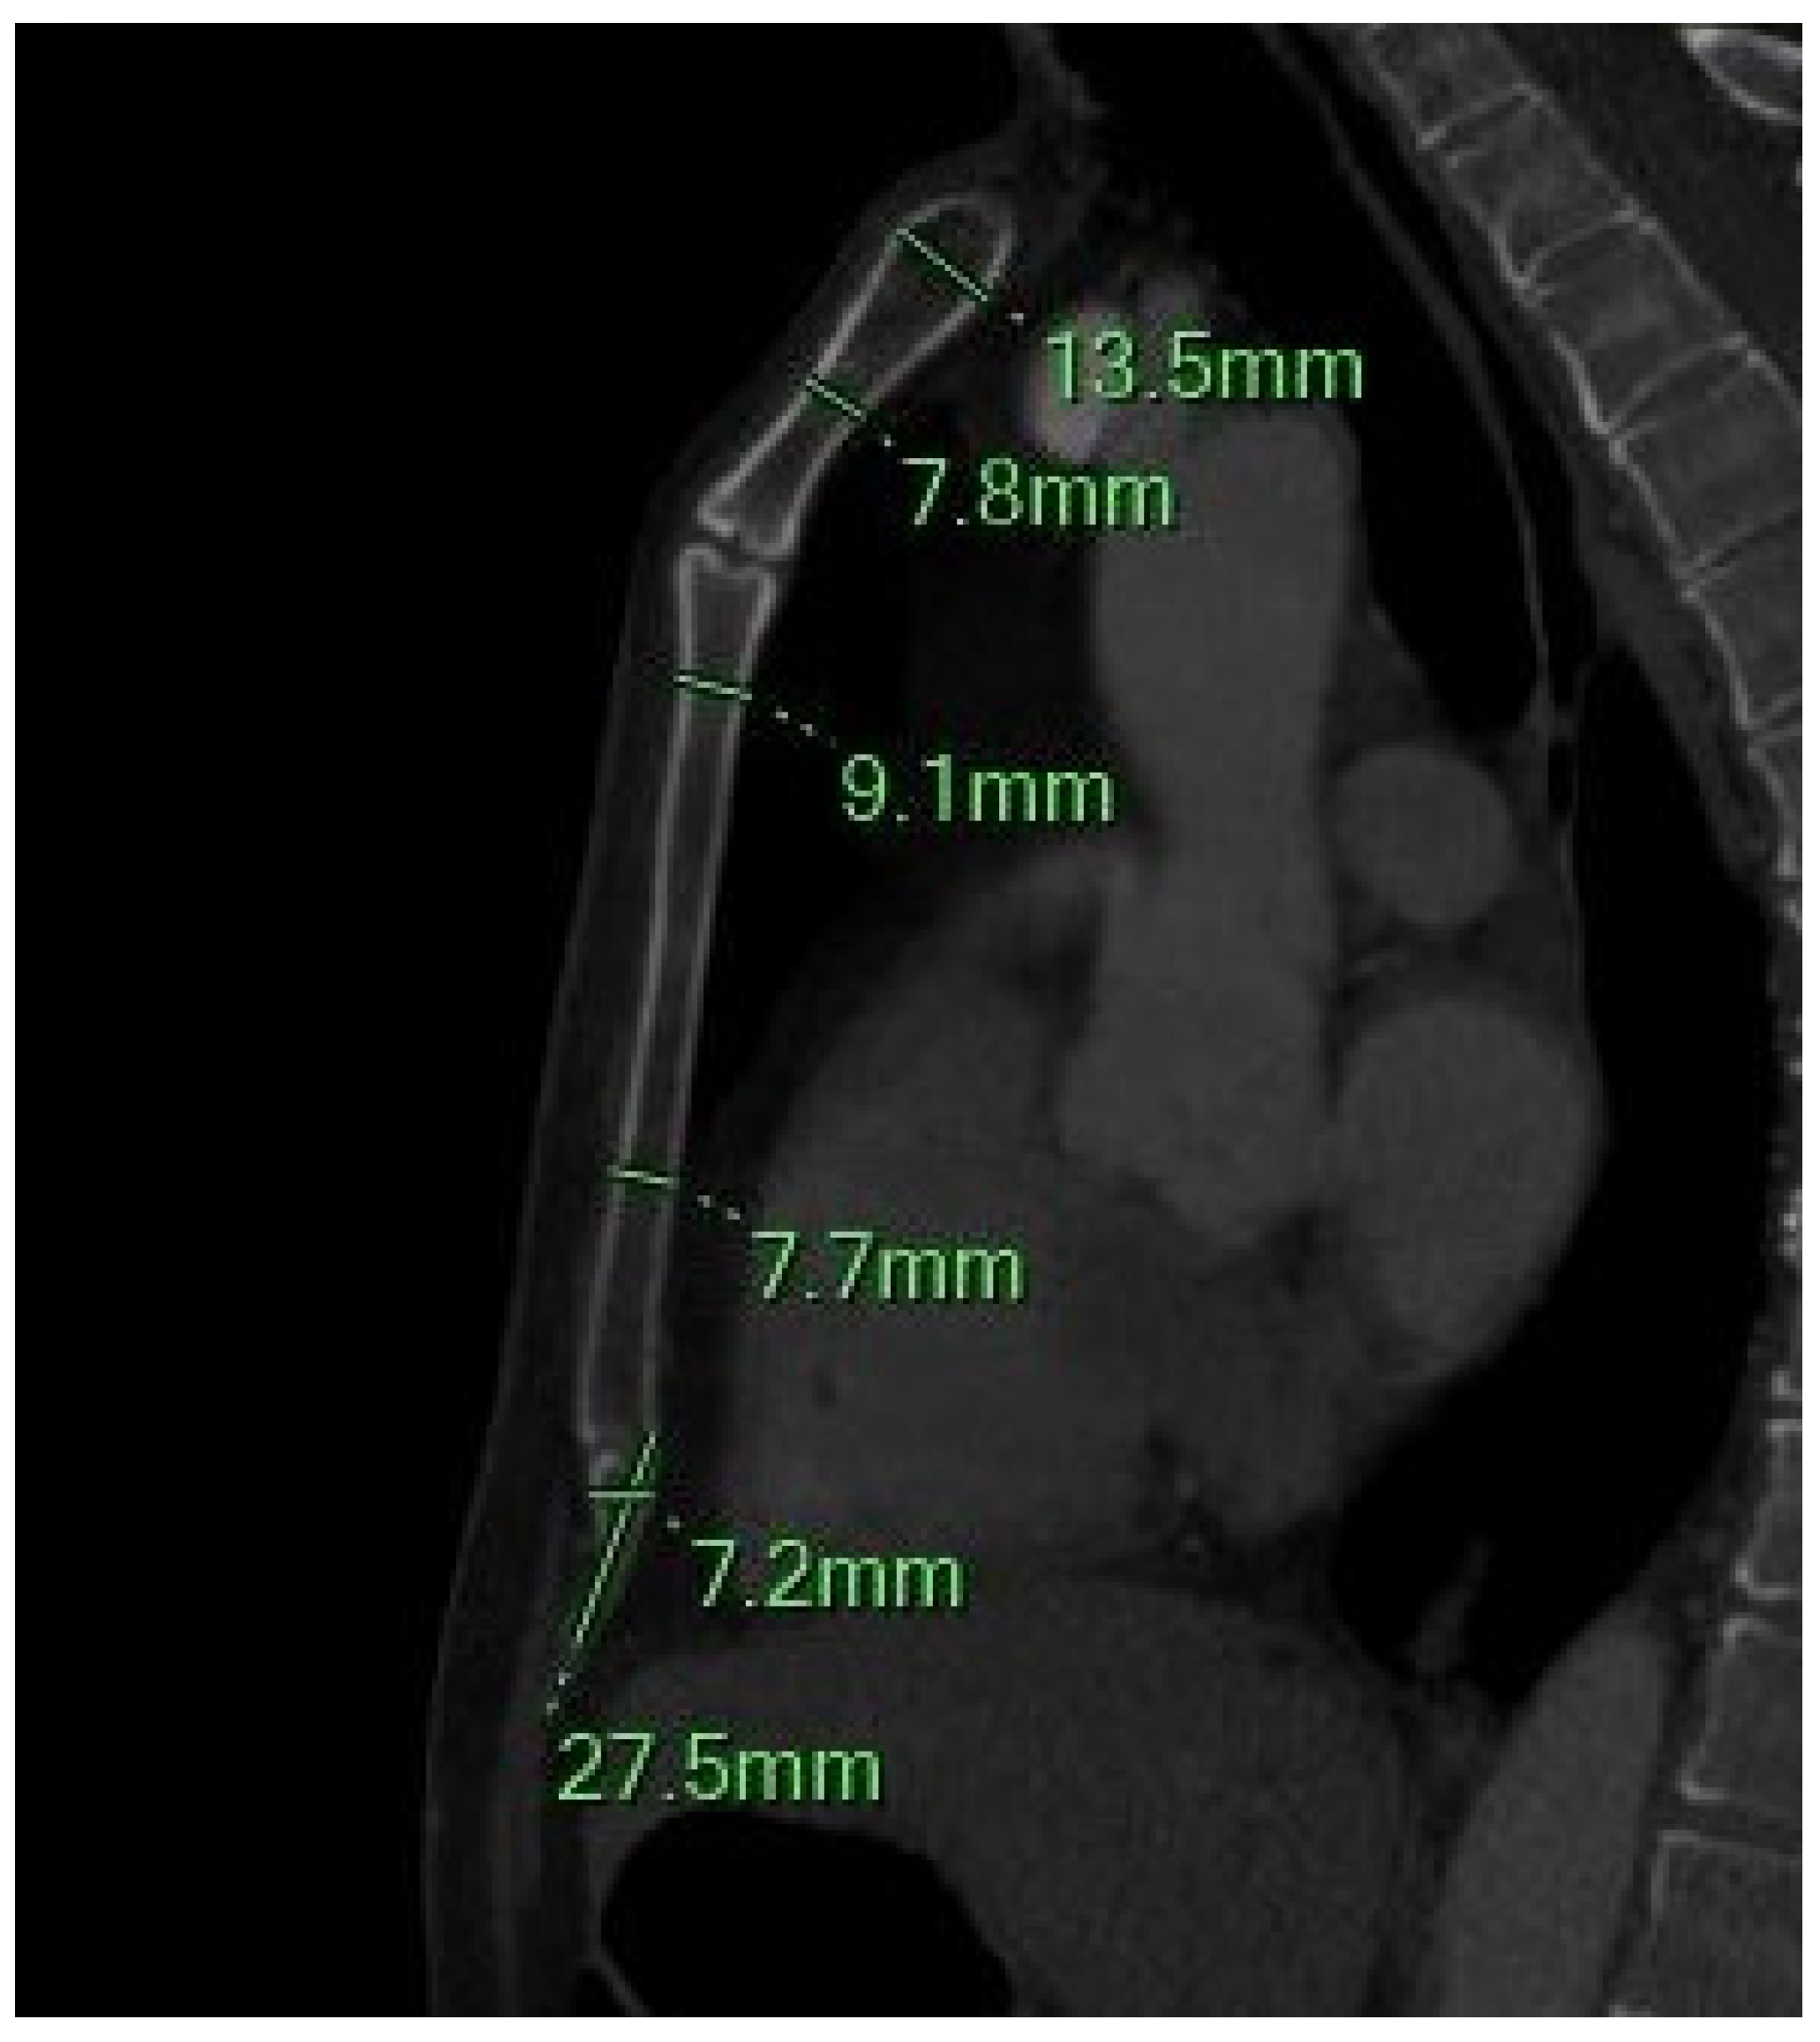

Figure 2.

The sagittal MIP MPR image shows the minimum and maximum thickness of the manubrium, the thickness of the sternal body between the 2–3 and 4–5 sternebrae, and the length and width of the xiphoid process.

- SB Thickness (SBT): Measured at the junctions of the 2nd–3rd and 4th–5th SBr, representing the anteroposterior depth.

2.4.3. Xiphoid Process (XP) Measurements

- -

- XP Length (XPL): Linear distance from the SXJ to the distal tip of the XP.

- XP Thickness (XPT): Maximum thickness measured between the SXJ and the XP’s distal endpoint.